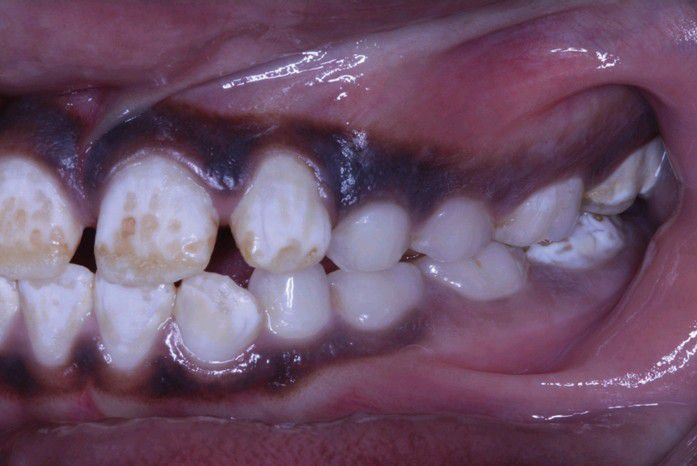

Flourosis

Dentition exhibiting lusterless, white, and opaque enamel with areas of chipping. Notice that the deciduous teeth are spared.